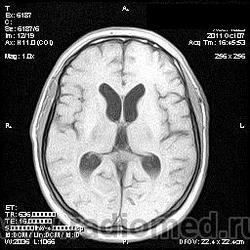

на МРТ - Определяется скопление крови в препонтинной цистерне, в проекции супраселлярной цистерны, в кортикальных бороздах полушарий головного мозга,  в проекции краниоспинального перехода. Выявляется горизонтальный уровень крови в задних рогах боковых желудочков. Боковые, третий желудочки резко расширены. Определяется перивентрикулярное повышение интенсивности сигнала от белого вещества головного мозга. Срединные структуры не смещены. Кортикальные борозды умеренно сглажены. Сильвиев водопровод прослеживается на всем протяжении. Отмечается смещение дна третьего желудочка каудально, с резким уменьшением размеров супраселлярной цистерны; базальные цистерны уменьшены в размере.

В проекции базальной артерии определяется аневризма размером до 4х6 мм.